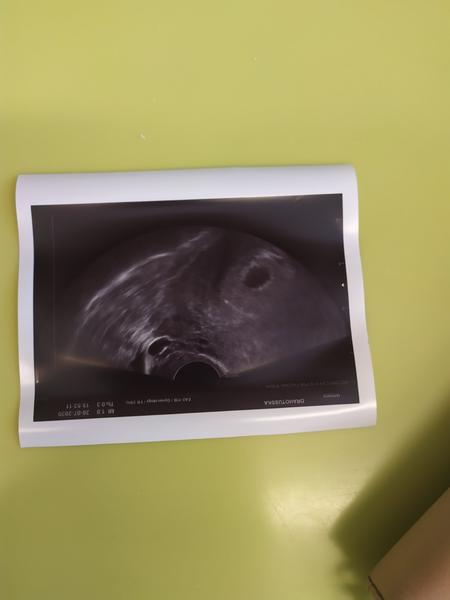

@sabinkanix holky, je v děloze,zatím vše v pořádku! Moc děkuji za podporu..bylo prostě jen brzo...